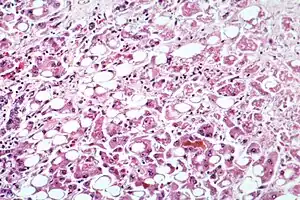

| Alcoholic hepatitis as seen with a microscope, showing fatty changes (white circles), remnants of dead liver cells, and Mallory bodies (twisted-rope shaped inclusions within some liver cells). (H&E stain) | |

Steatohepatitis is seen in both alcoholic and non-alcoholic liver disease and is the culmination of a cascade of events that began with injury. In the case of non-alcoholic steatohepatitis, this cascade is initiated by changes in metabolism associated with obesity, insulin resistance, and lipid dysregulation.[57][58] In alcoholic hepatitis, chronic excess alcohol use is the culprit.[59] Though the inciting event may differ, the progression of events is similar and begins with accumulation of free fatty acids (FFA) and their breakdown products in the liver cells in a process called steatosis.[57][58][59] This initially reversible process overwhelms the hepatocyte's ability to maintain lipid homeostasis leading to a toxic effect as fat molecules accumulate and are broken down in the setting of an oxidative stress response.[57][58][59] Over time, this abnormal lipid deposition triggers the immune system via toll-like receptor 4 (TLR4) resulting in the production of inflammatory cytokines such as TNF that cause liver cell injury and death.[57][58][59] These events mark the transition to steatohepatitis and in the setting of chronic injury, fibrosis eventually develops setting up events that lead to cirrhosis and hepatocellular carcinoma.[57] Microscopically, changes that can be seen include steatosis with large and swollen hepatocytes (ballooning), evidence of cellular injury and cell death (apoptosis, necrosis), evidence of inflammation in particular in zone 3 of the liver, variable degrees of fibrosis and Mallory bodies.[57][60][61]

Of note, liver biopsy shows identical findings in patients with ASH and NASH, specifically, the presence of polymorphonuclear infiltration, hepatocyte necrosis and apoptosis in the form of ballooning degeneration, Mallory bodies, and fibrosis around veins and sinuses.[28]